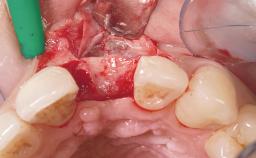

Immediate Flapless Placement of an Implant in a Maxillary Left Central Incisor Site

A 29-year-old female patient presented for treatment to replace the upper left central incisor tooth with an implant- supported restoration. The tooth had been intermittently symptomatic for the previous 12 months. The tooth had originally suffered trauma about 15 years previously. Several endodontic treatments had been performed, including an apicectomy procedure to retain the tooth. The patient was healthy and a non-smoker. She had reasonable expectations in regard to esthetic outcomes and the risk of marginal tissue recession following treatment. At medium smile, the gingival margins of the upper teeth were visible, with a display of 3 to 4 mm of the gingival margins. Gingival recession of tooth 21 and a discrepancy in the gingival levels between teeth 11 and 21 was observable during normal speech and smile.

Placement Protocol Immediate implant placement

Socket Integrity Damage to one or more bone walls

Bone Volume Damage to one or more socket walls